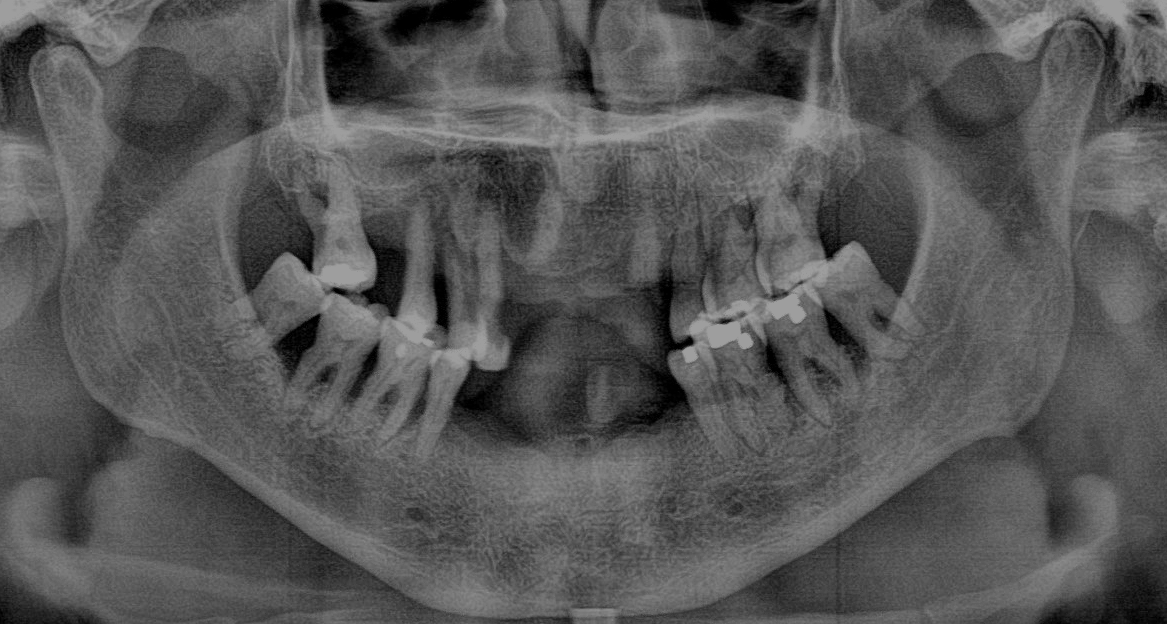

• A comprehensive exam, X-rays, and detailed impressions of your mouth are taken.

• These impressions are used to fabricate a customized immediate denture in advance, ensuring it is tailored to your smile and bite before extractions.

Who Is a Good Candidate for Dentures?

Dentures can be an excellent solution for patients looking to restore function, comfort, and confidence in their smile. However, the best option depends on individual oral health, bone structure, and personal preferences.

At Pelican Dental Care, we provide comprehensive evaluations to determine the best tooth replacement solution for your needs. Whether you’re considering traditional dentures, Snap-On Dentures, or All-On-Implants, our team is here to guide you.

• Are missing most or all of your teeth in the upper or lower arch.

• Have healthy gums and sufficient bone support for traditional or implant-supported dentures.

• Have severe, untreated gum disease – Healthy gums are essential for long-term denture support.

• Prefer a fixed, non-removable solution – All-On-Implants may be a better alternative for maximum stability.

• Have extensive bone loss – You may require bone grafting or implant-supported options for a secure fit.